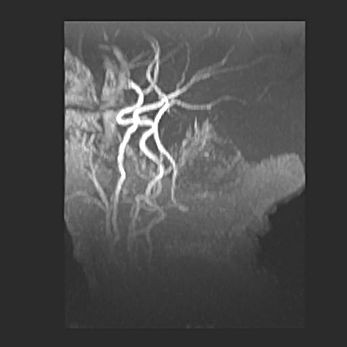

Мальформация Денди-Уокера. Киста задней черепной ямки.

Агенезия мозолистого тела.

Возраст: 2,5 месяца

Вес: 2420 г

Пол: женский

Окружность головы: 37 см

Срок гестации: 32 недели

Мальформация Денди—Уокера — редкий вид патологии ЦНС, представляющий собой врожденный порок развития каудального отдела ствола и червя мозжечка, ведущий к неполному раскрытию срединной (Мажанди) и латеральных (Лушка) апертур IV желудочка мозга. Для этогно синдрома характерна триада симптомов: гипотрофия червя мозжечка и/или полушарий мозжечка, кисты задней черепной ямки, гидроцефалия различной степени. В 70% случаев порок сочетается и с другими аномалиями головного мозга, в частности с агенезией мозолистого тела.